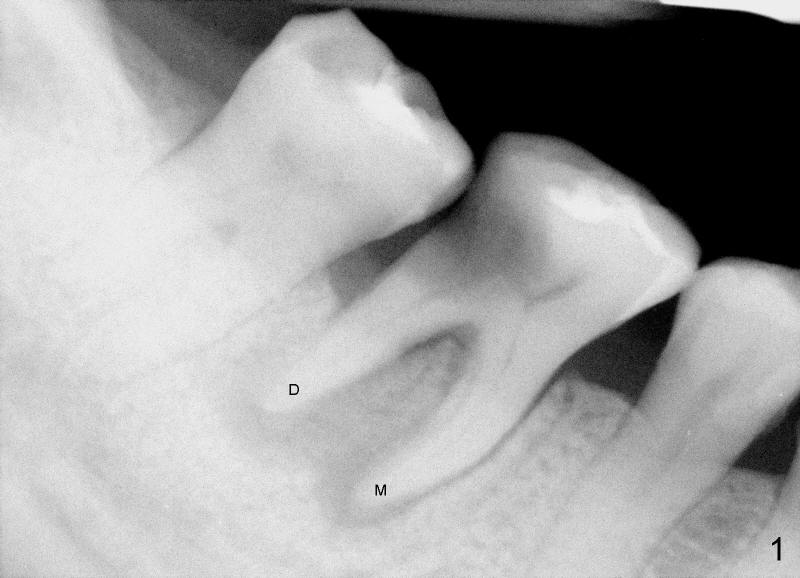

To further improve visibility, the arm of rubber dam clamp is changed from distal to mesial aspect of #30 (compare R in Fig.6 and 7). DL orifice is finally found, close to DB one. The DL canal is obliterated. It is debrided until #20 hand file short of WL. Fig.7 shows the chamber after RCT with gutta percha. * indicates thin pulpal floor. Fig.8 and 9 are taken after build-up (B). It appears that distal canals are divergent apically and that there are most likely two distal roots.